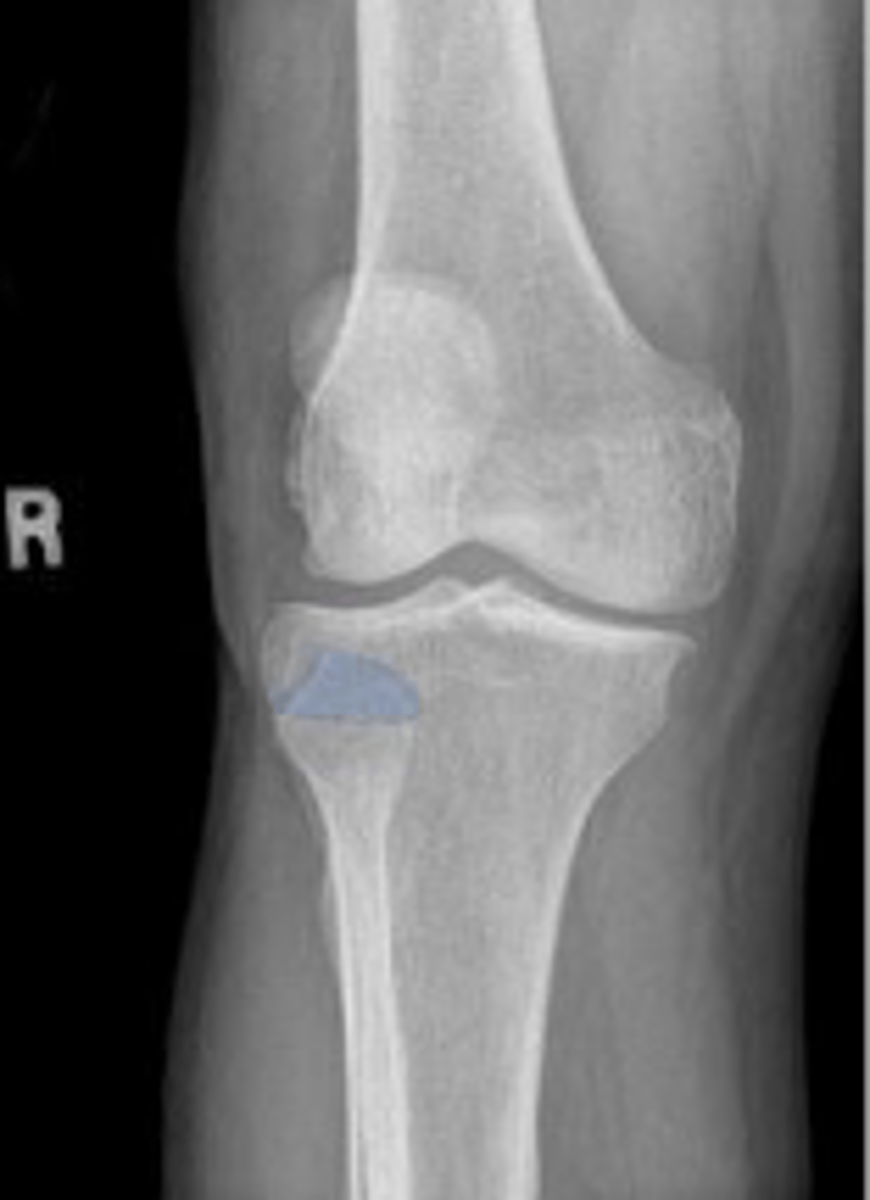

Right AP knee

What is the name of the radiographic view?

Medial condyle of the right femur

What is outlined?

Lateral condyle of the right femur

Intercondylar fossa/notch of the right femur

Lateral tibial spine/eminence

Medial tibial spine/eminence

Lateral tibial plateau of the right knee

Lateral tibial condyle of the right knee

Right lateral femorotibial joint space

What joint space is the arrowing pointing to?

The right medial & tibial plateaus and the right

medial and lateral condyles right knee